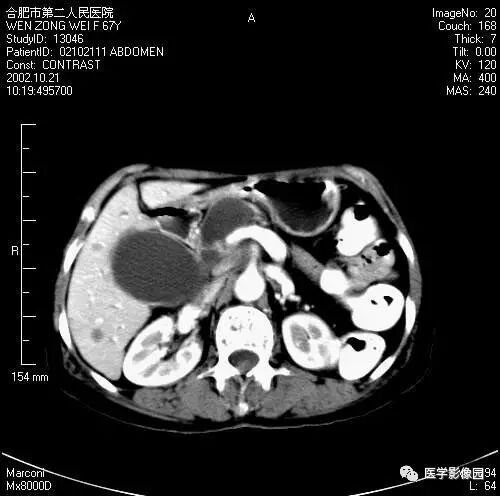

图6-4-12胰腺癌

增强扫描胰腺钩突失去正常平直的三角形,

呈不规则分叶状